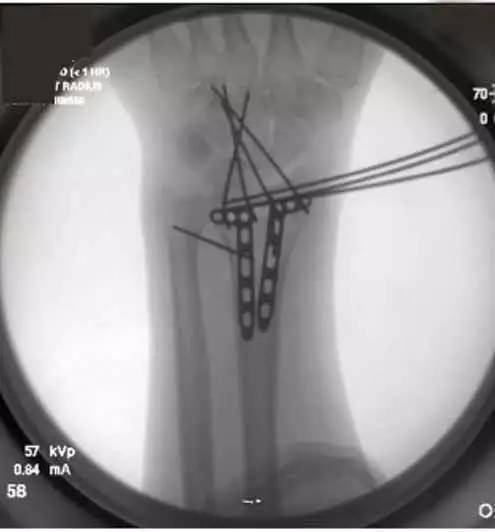

4. 固定后,使用显影纱布的显影条向远端牵拉背-掌侧向的克氏针,以维持远端关节面的复位(图 2)。

图 2 向远端牵拉背-掌侧向的克氏针